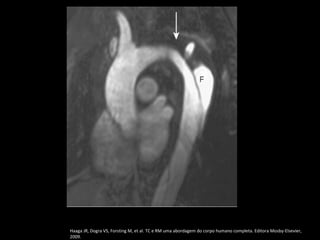

RM: T1 com gadolínio.

Pseudoaneurisma crônico

Haaga JR, Dogra VS, Forsting M, et al. TC e RM uma abordagem do corpo humano completa. Editora Mosby-Elsevier, 2009.